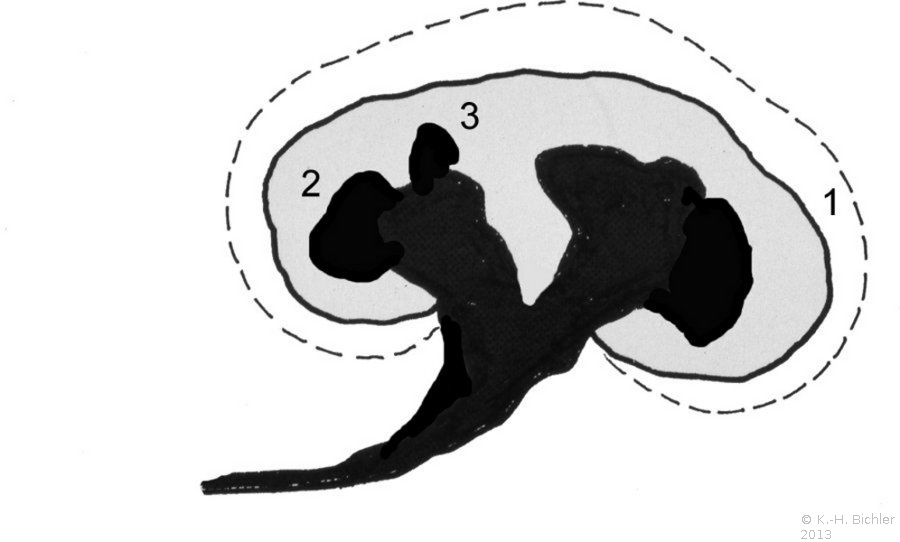

Die Refluxnephropathie ist von einer fortschreitenden Destruktion des Nierenparenchyms geprägt (Abbildung 7). Die pathologischen Veränderungen sind dabei abhängig vom Grad des Refluxes und oder der bakteriellen Infektion.

Die Nieren sind klein und haben ein Gewicht von ca. 40g. Die Nierenoberfläche ist diffus-höckrig. Refluxnarben finden sich an den Polen und der Mitte des Organs. Auf der Schnittfläche zeigt sich das Parenchym reduziert, z.T. mit abgeflachten Papillen und Bildung von Exkavationen bzw. Rezessi (Abbildung 7,8,9)

Beispiele Nieren mit ausgeprägter Refluxnephropathie.